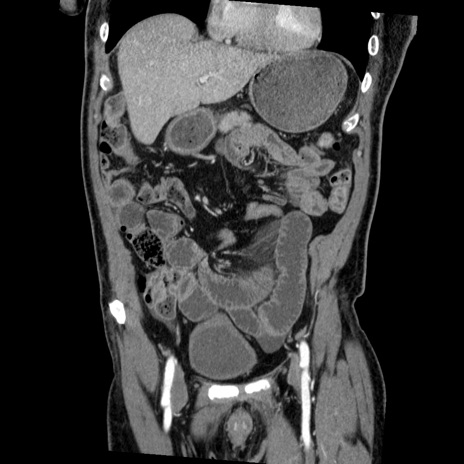

症例22(冠状断像)

【症例】50歳代男性

【主訴】腹痛

【現病歴】AVMからの被殻出血のため回復期リハ病棟入院中。 本日午後3時頃急に下腹部痛が出現した。

【既往歴】AVM、被殻出血、虫垂炎、高血圧

【身体所見】意識晴明、左半身不全麻痺、会話の理解は良好、36.5°C、腹部:膨隆、全体に板状硬、下腹部正中に圧痛点あり、反跳痛-、筋性防御不明、右下腹部にope scar

【データ】WBC 9400、CRP 0.06